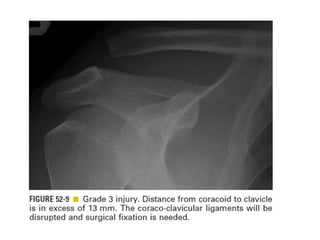

Skeletal trauma was presented by Dr Laith Fadhel with reference to Grainger's Diagnostic Radiology textbook. The presentation covered skeletal trauma as assessed through diagnostic radiology techniques. Key findings and treatments for skeletal injuries were likely discussed.